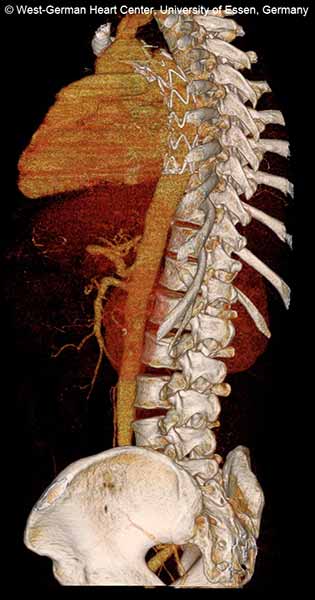

| FIGURE 1-3: 2D and 3D preoperative CT Images of a 78 year old man with aortic insufficiency, and ascending, arch and descending aortic aneurysm with mural thrombus. | |

Appropriate patients for this procedure have extensive thoracic aortic disease and a suitable landing zone for a stent graft in the descending aorta. Many of these patients are candidates for a 2-stage procedure, and selection is based on expected outcomes and the estimated interval rupture risk if patients were to be treated in a staged fashion. (see Figs. 1-3)